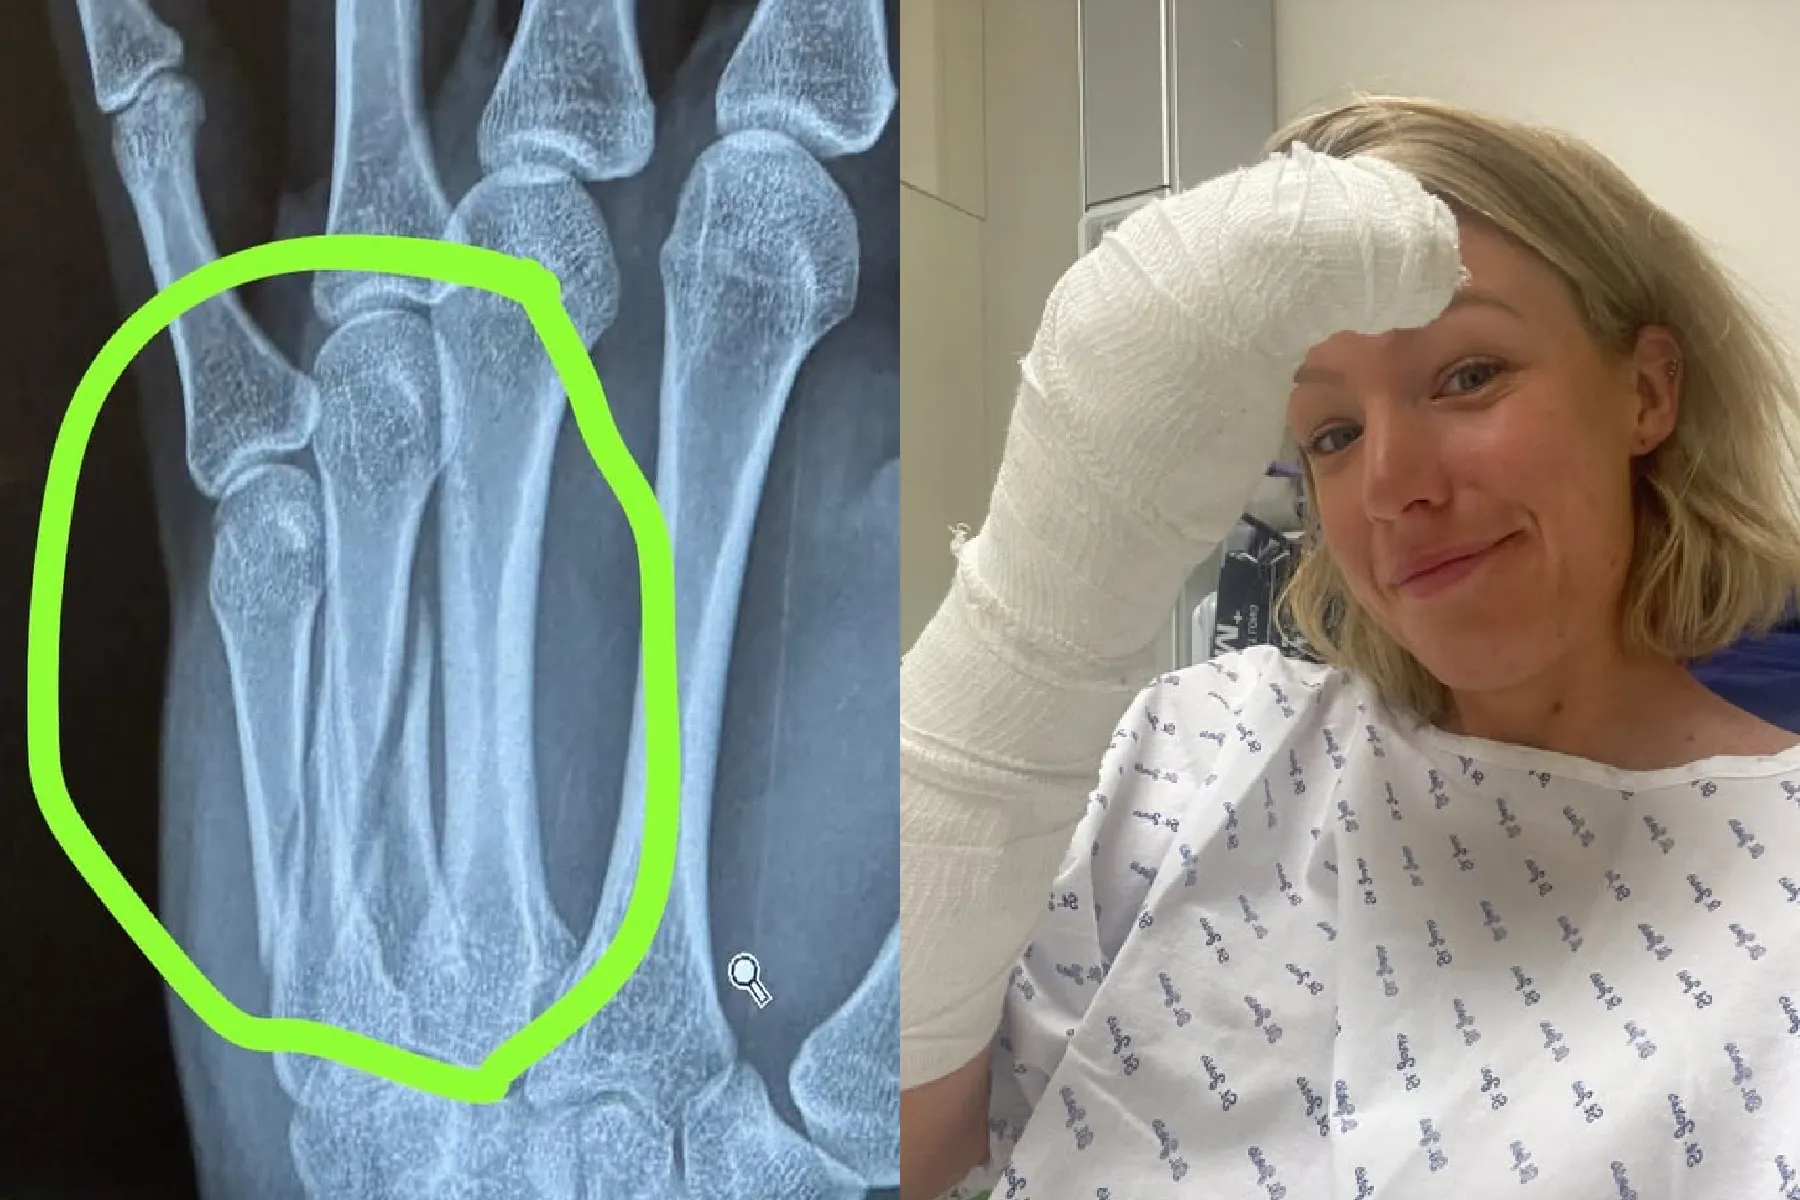

'Een grote tegenslag': Worst loopt breuken in hand op in Zonhoven tijdens 'cruciale fase van cross-seizoen'

24 december 2024

Bram van der Ploeg

Worst terug op de fiets, maar dan wel indoor: 'We hebben nog steeds enkele doelen voor dit seizoen'

11 januari 2025

Jesse van Dalen